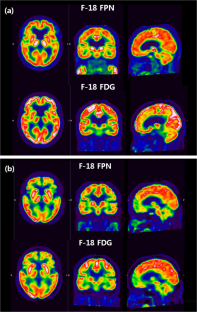

Correlation of Early-Phase F-18 Florapronal PET with F-18 FDG PET in Alzheimer’s Disease and Normal Brain

F-18 florapronol (FPN) is the commercially recognized beta-amyloid positron emission tomography (PET) radiotracer in Korea. This study compared the early F-18 florapronol PET with F-18 fluorodeoxyglucose (FDG) PET between healthy controls (HC) and Alzheimer’s dementia (AD) patients.

We compared the F-18 FDG and F-18 FPN for SUVR of a specific region in global mean normalization and cerebellum normalization, and most of the correlation coefficient was higher in global mean normalization. In global mean normalization, the correlation coefficient for SUVR of HC was higher than that of AD in all brain regions.

Early F-18 FPN study can be used as a proxy marker for the F-18 FDG PET.